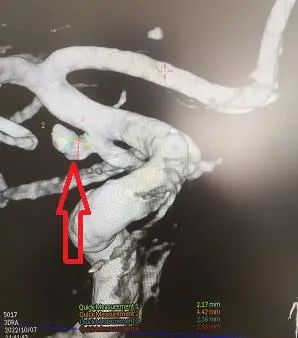

神经外科二组主任王宝庆带领副主任医师郭知伟和住院医师王尧迅速为患者做了脑血管造影,DSA检查结果显示:颅内动脉瘤(右侧颈内动脉交通段动脉瘤,与头部CT显示出血吻合)。病因明确了,动脉瘤破裂出血是本次发病的罪魁祸首。但是患者脑部血管为典型的“三型弓”,介入治疗动脉瘤导管到位十分困难,但考虑到脑动脉瘤的危害,如果第二次破裂出血的死亡率达到50%以上,患者将随时面临死亡的危险,会引起脑积水、脑出血等并发症。王宝庆主任根据病人特点与患者家属充分沟通,建议手术治疗,言简意赅地介绍了介入和开刀两种手术方式的利弊,最终家属选择开颅夹闭动脉瘤。

王宝庆团队术前经过了充分的准备,做好手术预案,为患者做了后交通动脉瘤开颅夹闭术,消灭了本次蛛网膜下出血的责任病灶。动脉瘤夹闭满意,载瘤动脉通畅,颅内血管无损伤,血供良好。手术顺利,术后病人清醒,语言、肢体感觉运动功能良好。